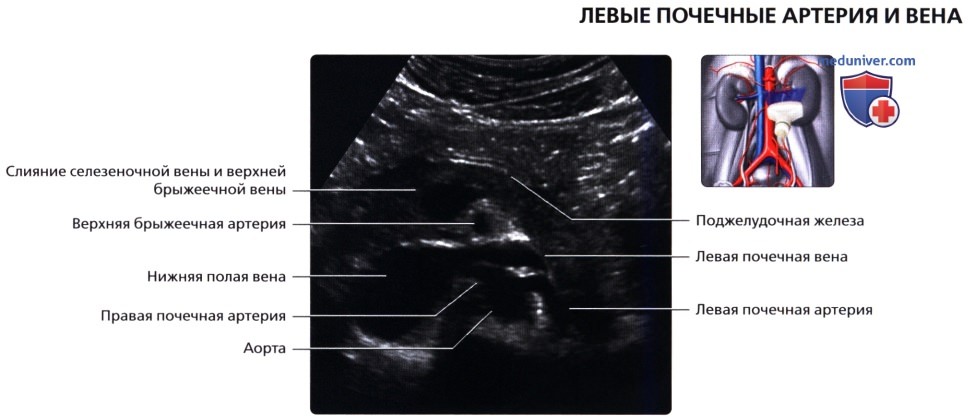

• Кровеносные и лимфатические сосуды, нервы:

о Артерия:

— Обычно по одной к каждой почке

— Отходит от аорты на уровне L1-L2 позвонков

о Вена:

— Обычно по одной от каждой почки

— Лежит кпереди от почечной артерии и почечной лоханки

• Почечные артерии:

о Места отхождения лучше всего визуализируются при сканировании по срединной линии спереди

о Правую почечную артерию обычно можно проследить от места отхождения до почки

о Для визуализации левой почечной артерии часто требуется установить датчик на заднебоковой поверхности во фронтальной проекции

• Почечные вены:

о Лучше всего визуализируются при поперечном трансабдоминальном сканировании

о Также могут быть видны при сканировании в фронтальной плоскости с заднебоковой поверхности